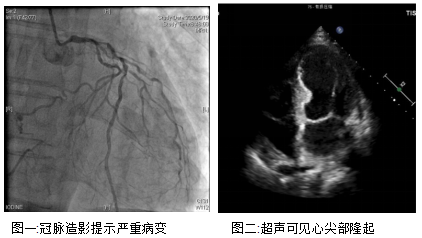

老孙就是同时被冠心病和室壁瘤困扰的患者。3年前他便出现了胸闷、憋气的症状,半年前症状加重了,在清华⻓庚医院做了造影,证实是严重的左主干+三支病变,必须做冠脉搭桥才有望改善心脏缺血的现状。但老孙的心功能却不容乐观,射血分数只有30%,仅仅相当于正常人的一半,而且超声还可以看到老孙的心尖部变得薄而圆钝,心脏跳动时几乎不运动,提示他还有室壁瘤形成。

辗转就诊于北京两大心脏中心,都因病情重而被婉拒。针对老孙这种特殊情况,负责主诊的崔晓征医师与李温斌主任共同商议治疗方案,从患者实际利益出发,以“改善患者心肌缺血,提高患者心脏功能”为原则,决定在术中探查室壁瘤的范围,完全切除室壁瘤,减少心脏的无效做功,提高其心脏收缩功能,随后根据切除后剩余心肌的范围进行搭桥手术,改善其余心肌的供血,进一步改善其心脏功能。 在完善各项检查,充分预估手术⻛险后,老孙在本月21日做了室壁瘤切除修补术+冠脉搭桥手术。整个手术仅用时5小时,最大限度地减少了患者麻醉的⻛险。目前,患者尚在监护室恢复中,状态平稳。